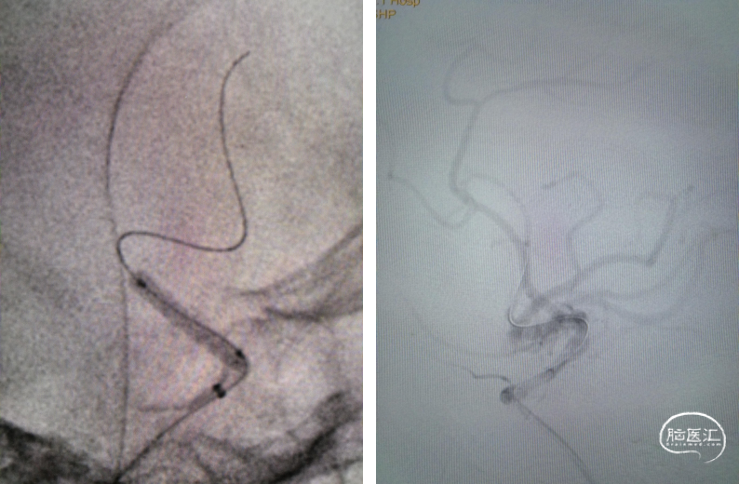

重要操作简述:支架定位和防止微导丝移位;防止支架移位,缓慢释放支架,压力6ATM。

支架覆盖病变

支架释放

术后影像及检查

影像结论:无残余狭窄,无异常密度影。

术后Tlcl:3级。

影像结论:颅内血管显影良好,无栓塞或造影剂外渗,支架形态良好。术后复查CT无脑出血。